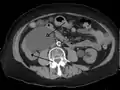

Hydronephrosis due to a kidney stone at the ureteral vesicular junction seen on CT scan

The choice of imaging depends on the clinical presentation (history, symptoms and examination findings). In the case of renal colic (one sided loin pain usually accompanied by a trace of blood in the urine) the initial investigation is usually a spiral or helical CT scan. This has the advantage of showing whether there is any obstruction of flow of urine causing hydronephrosis as well as demonstrating the function of the other kidney. Many stones are not visible on plain X-ray or IVU but 99% of stones are visible on CT and therefore CT is becoming a common choice of initial investigation. CT is not used however, when there is a reason to avoid radiation exposure, e.g. in pregnancy.